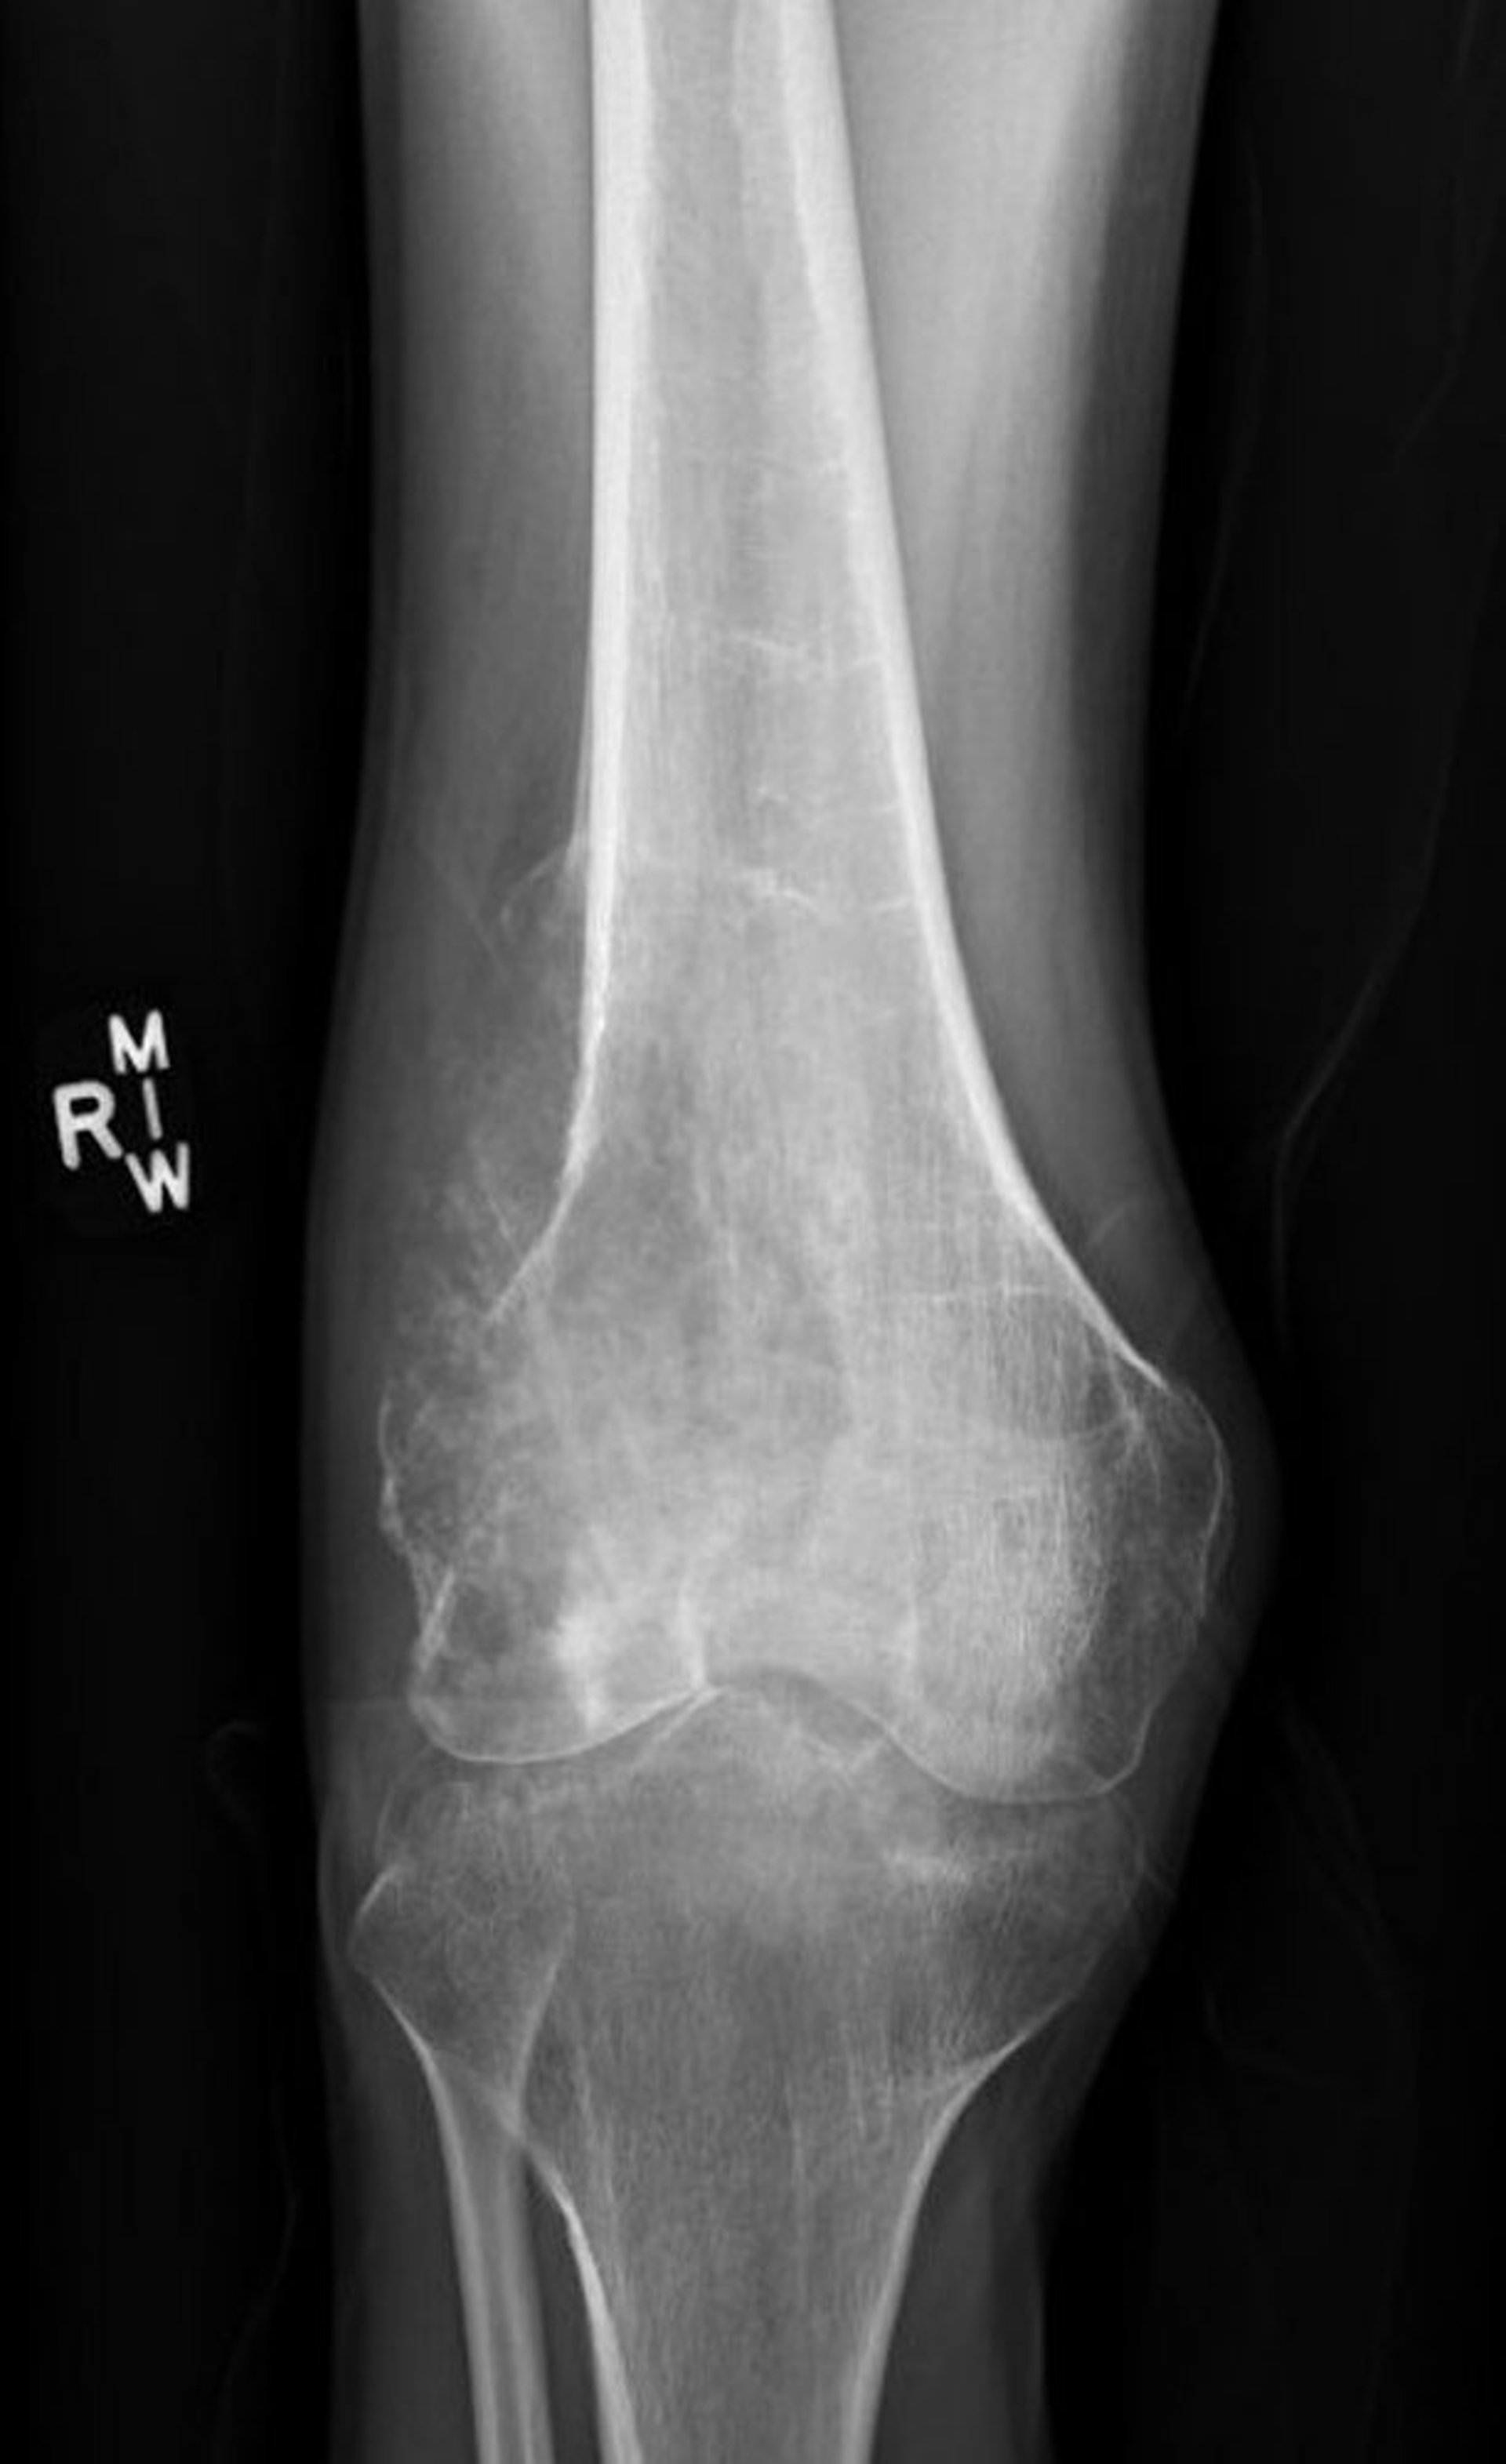

Osteosarcomas, por lo general, se presentan en la rodilla o alrededor de esta, aunque se pueden originar en cualquier hueso. Tienden a extenderse (metastatizar) a los pulmones o a los otros huesos. Usualmente, estos tumores causan dolor, hinchazón o una acumulación de tejido blando, y pérdida de movimiento articular.

Se realizan radiografías, pero el diagnóstico de osteosarcoma requiere la extracción de una muestra de tejido para su examen al microscopio (biopsia). Para detectar las metástasis del cáncer en el pulmón se necesita una radiografía de tórax y una tomografía computarizada (TC) y para detectar el cáncer que se ha extendido a otros huesos se necesita una gammagrafía ósea. La resonancia magnética nuclear (RMN) y la tomografía por emisión de positrones (PET) en combinación con la tomografía computarizada (PET-TC) son otras de las pruebas de diagnóstico por la imagen que también se pueden solicitar.

Esta radiografía de la rodilla muestra un osteosarcoma en el hueso del muslo (fémur), por encima de la rodilla.

Imagen cortesía de Lukas Nystrom, MD.

Más del 65% de las personas que tienen este tipo de tumor sobreviven al menos 5 años después del diagnóstico si han recibido quimioterapia y el cáncer no ha hecho metástasis. Si la quimioterapia destruye casi todo el cáncer, la probabilidad de sobrevivir al menos 5 años es mayor del 90%. Debido a la mejora de las técnicas quirúrgicas, el brazo o la pierna afectados pueden frecuentemente salvarse y reconstruirse. En el pasado, por lo general, la extremidad afectada tenía que ser amputada.

Los osteosarcomas suelen tratarse con una combinación de quimioterapia y cirugía. Habitualmente se administra primero la quimioterapia. El dolor disminuye con frecuencia durante esta fase del tratamiento. Después el tumor se extirpa quirúrgicamente sin cortarlo. Si se cortara el tumor, sus células se diseminarían, lo que podría provocar la vuelta del cáncer a la misma zona. La quimioterapia continúa después de la cirugía.